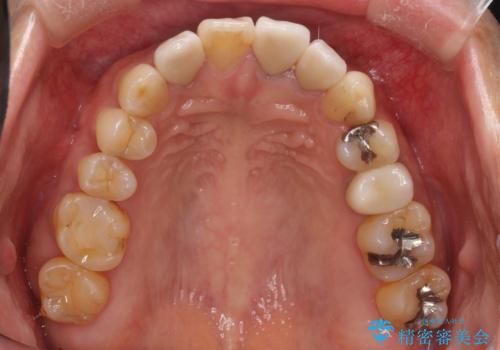

- 全体的なガタガタと前歯をきれいにしたいとのことで来院されました。

下の歯は重度のガタガタがあり、上の前歯は何本かが神経の治療がしてある状態でした。

インビザラインにて歯並びを整え、上顎の前歯にセラミックを装着する計画としました。

セラミックと矯正を組み合わせることにより、審美的にも機能的にも改善することができました。